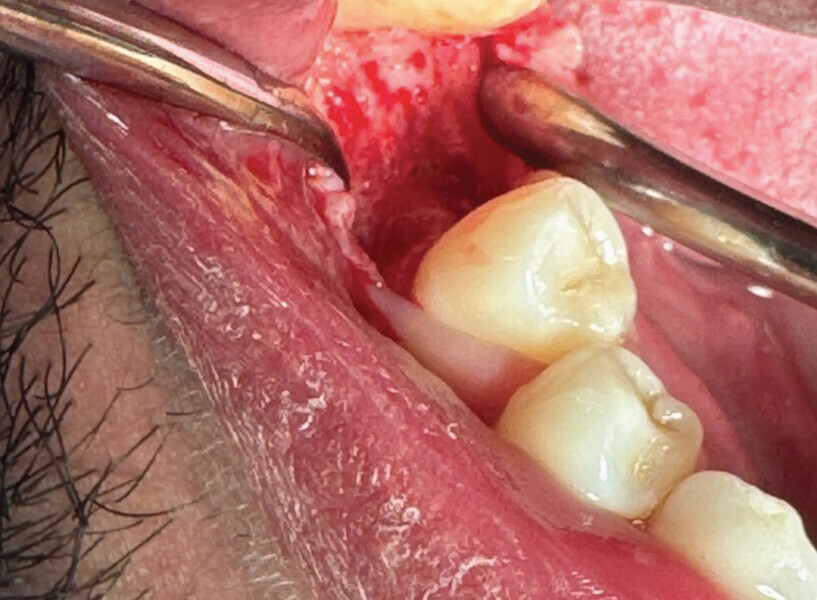

L’avulsion a été faite après anesthésie avec une ampoule de SEPANEST 40 mg adrénaline à 1/200000e. L’acte chirurgical est réalisé de manière la plus atraumatique possible, exérèse et curetage du kyste apical, nettoyage de l’alvéole. Dans ce cas précis, nous n’avons rien mis dans l’alvéole car les quatre murs alvéolaires ont pu être conservés. Un léger décollement des muqueuses vestibulaires et linguales a été nécessaire pour la mise en place de la membrane R.T.R.+.* La structure de cette membrane est faite pour être positionnée dans un sens précis, la surface lisse est toujours positionnée vers l’extérieur et la face rugueuse en regard de l’os.

Fig. 2

C’est sa structure et composition spécifique qui va permettre la non-compétition cellulaire et par la même la constitution de l’os sous la membrane. Les cellules épithéliales vont, quant à elles, se développer en tapissant la surface lisse de cette membrane (Figs. 2 et 3).